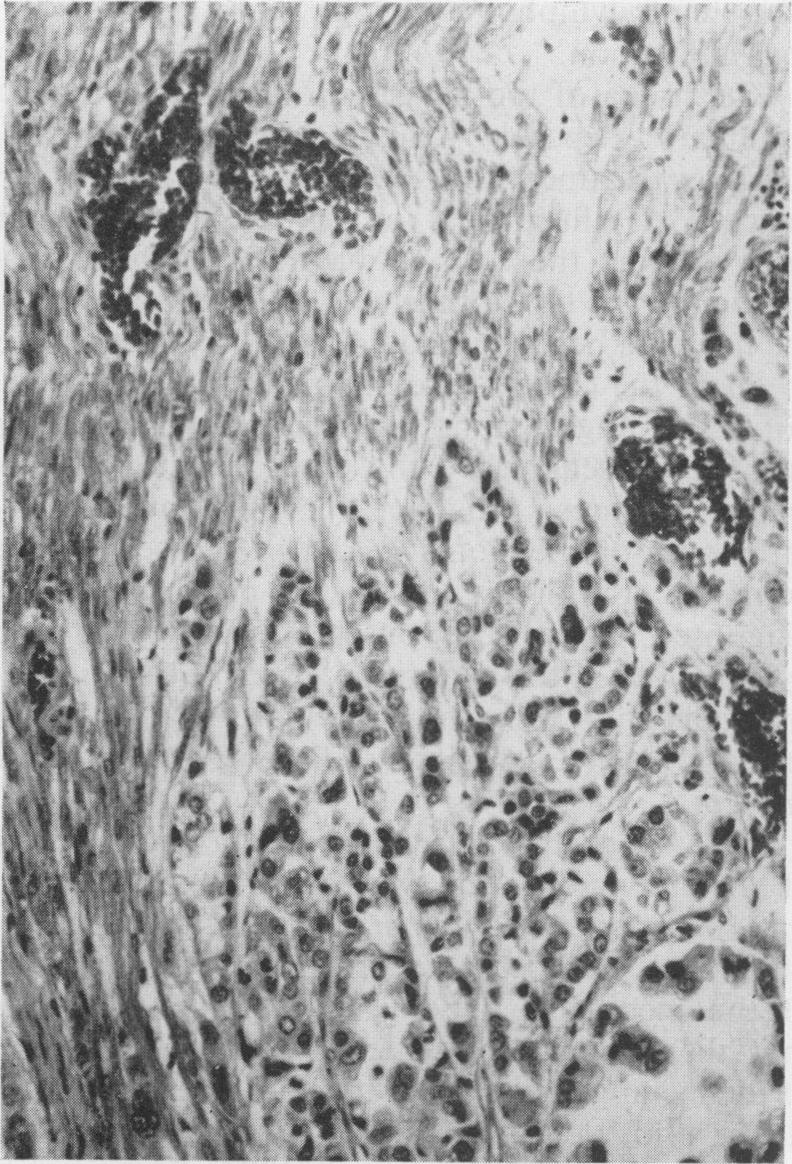

The clinical and pathological features of 63 cases of post-mortem-proved diffuse infiltration of the leptomeninges by tumour are presented. A wide variety of tumours of the nervous system, both primary and secondary, was found to give rise to such involvement, with adenocarcinoma having a particular propensity to behave in this manner. Dysfunction of cranial and spinal nerves, a confusional state and headache were prominent clinical features. Examination of the cerebro-spinal fluid was found to be less useful diagnostically in cases of primary tumours of the nervous system with leptomeningeal involvement than in cases of diffuse infiltration of the meninges by carcinoma.